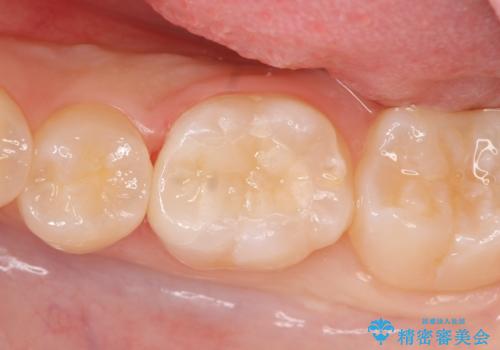

う蝕を丁寧に除去したのち、セラミックインレーによる修復を行いました。

セラミックインレーの審美的な仕上がりと自然な咬み心地にご満足頂けました。

インレーの種類:セラミックインレー(e-max press)